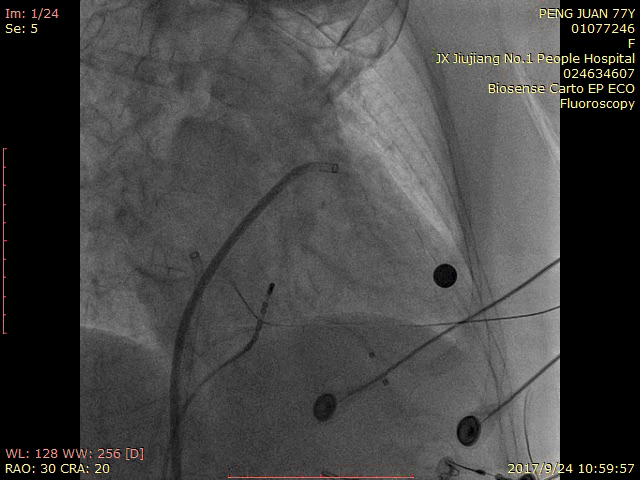

术中造影:

RAO 30 CRA 20:

RAO 30 CAU 20:

RAO 30 CAU 20 Fish Ball造影:

RAO 30 CAU 20 牵拉试验: